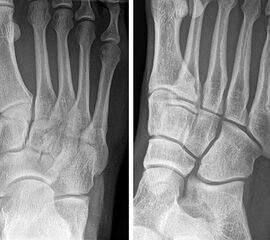

Lawrence und Botte Zone III

Weitestgehende Einigkeit besteht bei der OP-Indikation für metadiaphysäre Frakturen (Lawrence und Botte Zone III, Abb. 5) 20721. Exemplarisch sei hier die Studie von Mologne und Kollegen 21 genannt. Im Rahmen einer randomisierten kontrollierten Studie wurde eine restriktive konservative Behandlung (Entlastung und Gips, n=18) gegen eine operative Therapie (Schraubenosteosynthese, n=19) verglichen (Follow-up: 25 Monate). Dabei zeigte sich eine deutliche Überlegenheit der operativen Behandlung.

Stressfrakturen der MT V Basis werden häufig als eigene Entität beschrieben (Abb. 6). Allerdings kommen diese Frakturen hauptsächlich in der Zone III nach Lawrence und Botte vor (Khan, 2006). Eine systematische Literaturarbeit von Mallee und Kollegen 14 verglich die konservative und operative Therapie bei Patienten mit Stressfrakturen der MT V Basis. Basierend auf den Ergebnissen von 8 Studien konnten die Autoren auch hier eine Überlegenheit der operativen Therapie zeigen.